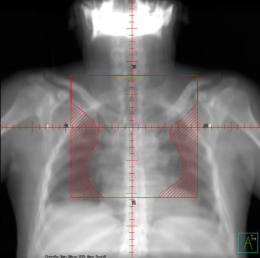

identify a Digitally Reconstructed Image (DRR)

What type of image is this?

conventional sim film